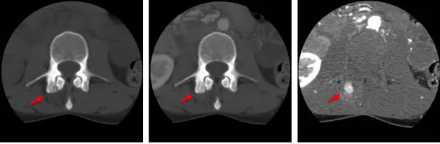

骨智能柔性減影成像功能發(fā)現隱匿骨占位病灶

相比傳統(tǒng)成像方式,肺部柔性減影技術通過人工智能,對平掃數據和CT肺動脈血管掃描數據進行智能比對,解碼并識別各個器官(肺、氣管、肺動脈、肺靜脈、主動脈等)的空間位置,并在三維空間中進行體素級的柔性配準,從而極大提升了不同序列數據的空間位置的一致性。通過肺部柔性減影技術可得到肺強化碘圖,可以顯示出傳統(tǒng)CTPA圖像看不到的小栓塞病變,提高了栓塞檢出率,其結果甚至可與SPECT吻合。

肺智能柔性減影成像功能發(fā)現亞段肺栓塞